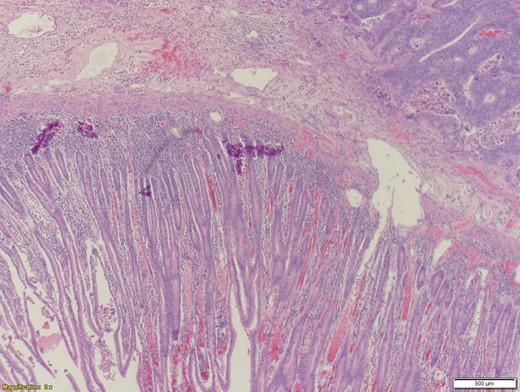

A 70-year-old female presented to the emergency department with complaints of diarrhea, vague, dull abdominal pain, unintentional weight loss and poor appetite. No hematochezia or melaena stated. Fecal occult is strongly positive in the ED. No endoscopies were found in her records. PMHx included COPD, osteoarthritis and DVT. Significant physical exam findings included mild, diffuse abdominal tenderness and RUQ palpable mass, and normal bowel sounds. Labs were significant for a hemoglobin of 5.7, hematocrit of 18.6% and CEA of 29.6. An abdominal/pelvis CT exhibited a 6 cm circumferential mass of the hepatic flexure (Figs 1–3). Two days later, a right hemicolectomy with en bloc pancreaticoduodenectomy was performed. Pathology showed adenocarcinoma stage IIIc (Figs 4–10). Post-operatively, an abdominal/pelvis CT showed bilateral pulmonary emboli and a 14 cm pelvic abscess. Bilateral lower extremity ultrasound showed low probability for DVT. Exploratory laparotomy was performed where the pelvic abscess was seen and extensive lysis of adhesions, resection of ileocolonic anastomosis for contained leak and ileostomy performed. Approximately 4 months after discharge, the patient passed away while in a long-term care facility.